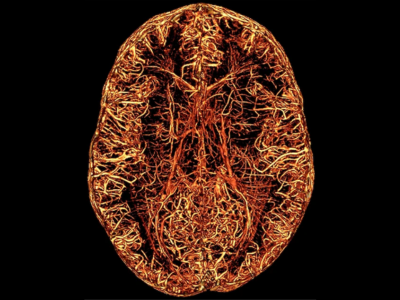

No 17 | Les vaisseaux du souvenir